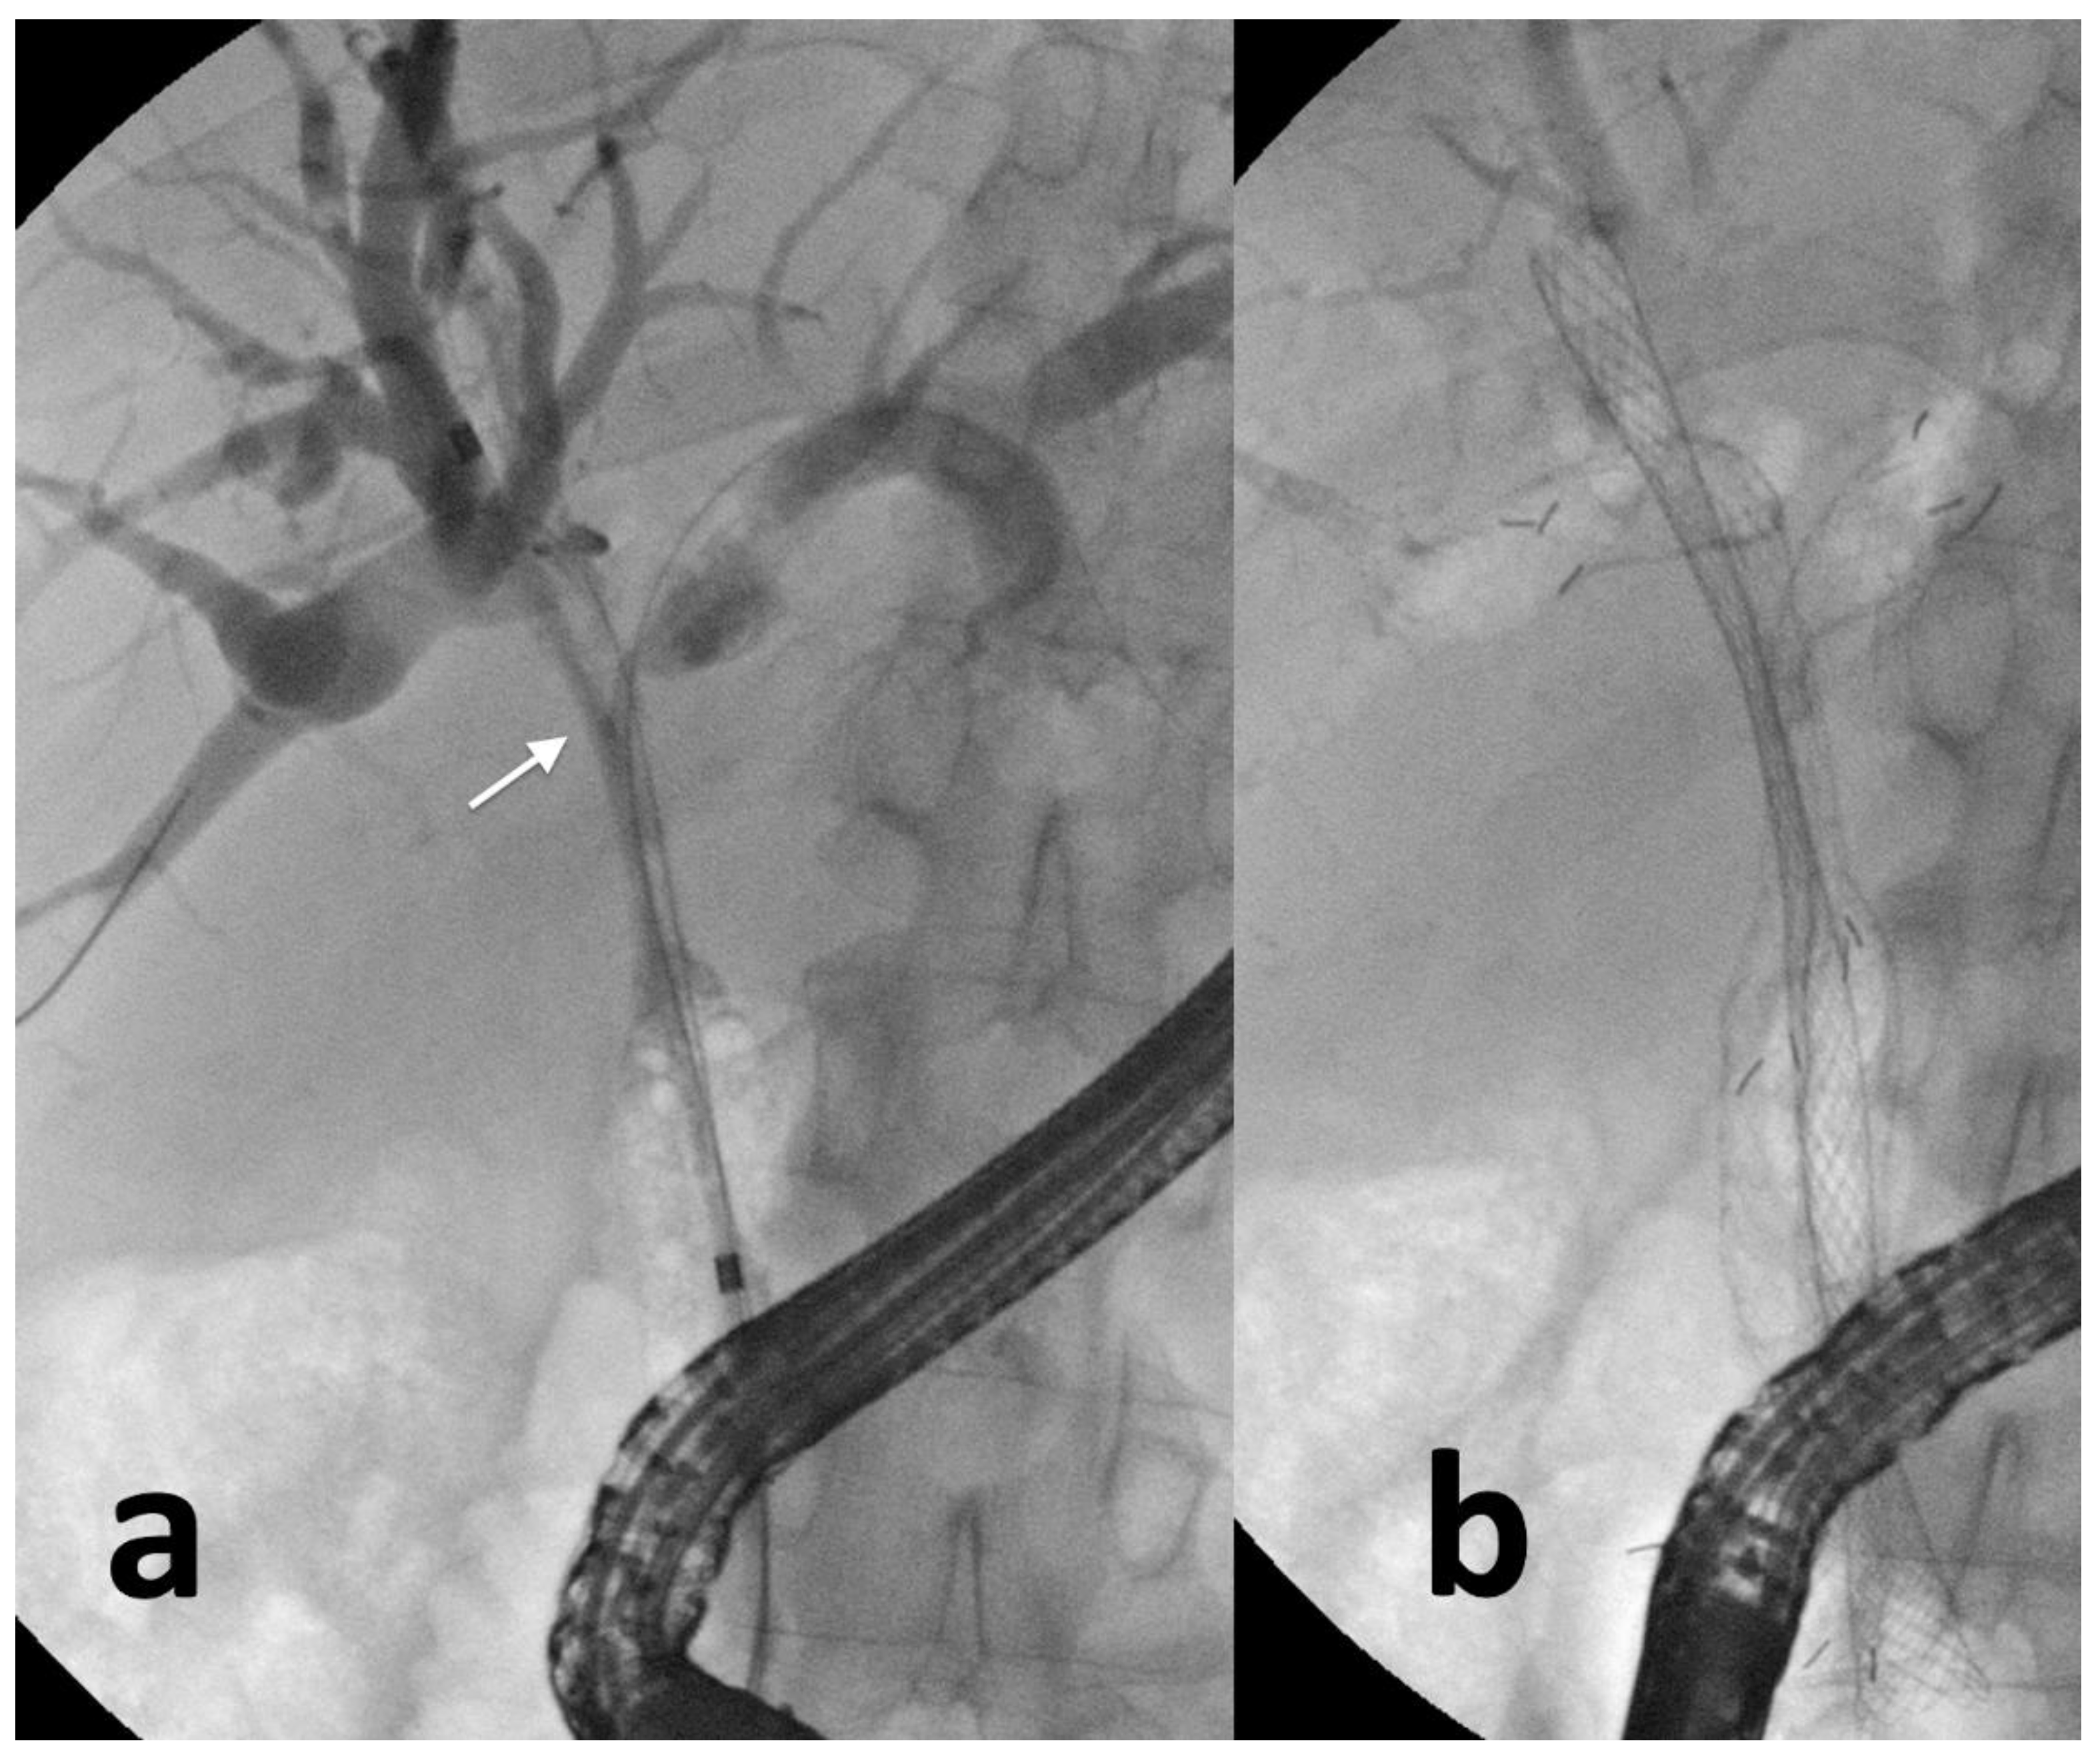

2.1. ERCP-Guided Biliary Drainage

- Boškoski, I.; Schepis, T.; Tringali, A.; Familiari, P.; Bove, V.; Attili, F.; Landi, R.; Perri, V.; Costamagna, G. Personalized Endoscopy in Complex Malignant Hilar Biliary Strictures. J. Pers. Med. 2021, 11, 78. [Google Scholar] [CrossRef]

- Gao, D.J.; Hu, B.; Ye, X.; Wang, T.T.; Wu, J. Metal versus plastic stents for unresectable gallbladder cancer with hilar duct obstruction. Dig. Endosc. 2017, 29, 97–103. [Google Scholar] [CrossRef]